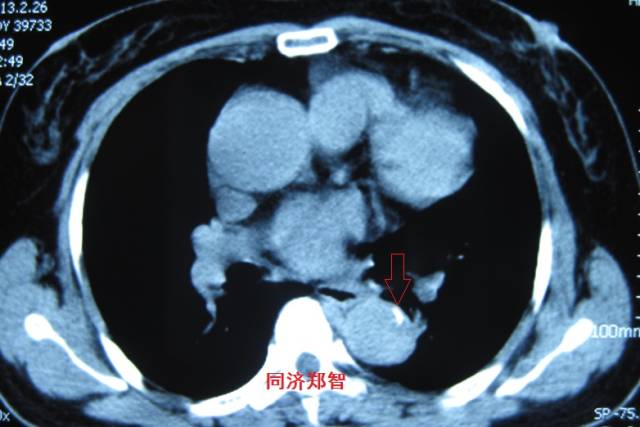

病例十

腹主动脉平扫CT提示正常外周一圈的钙化影中有内移的钙化影(红色箭头所示),CTA 证实为腹主动脉夹层

图19-20